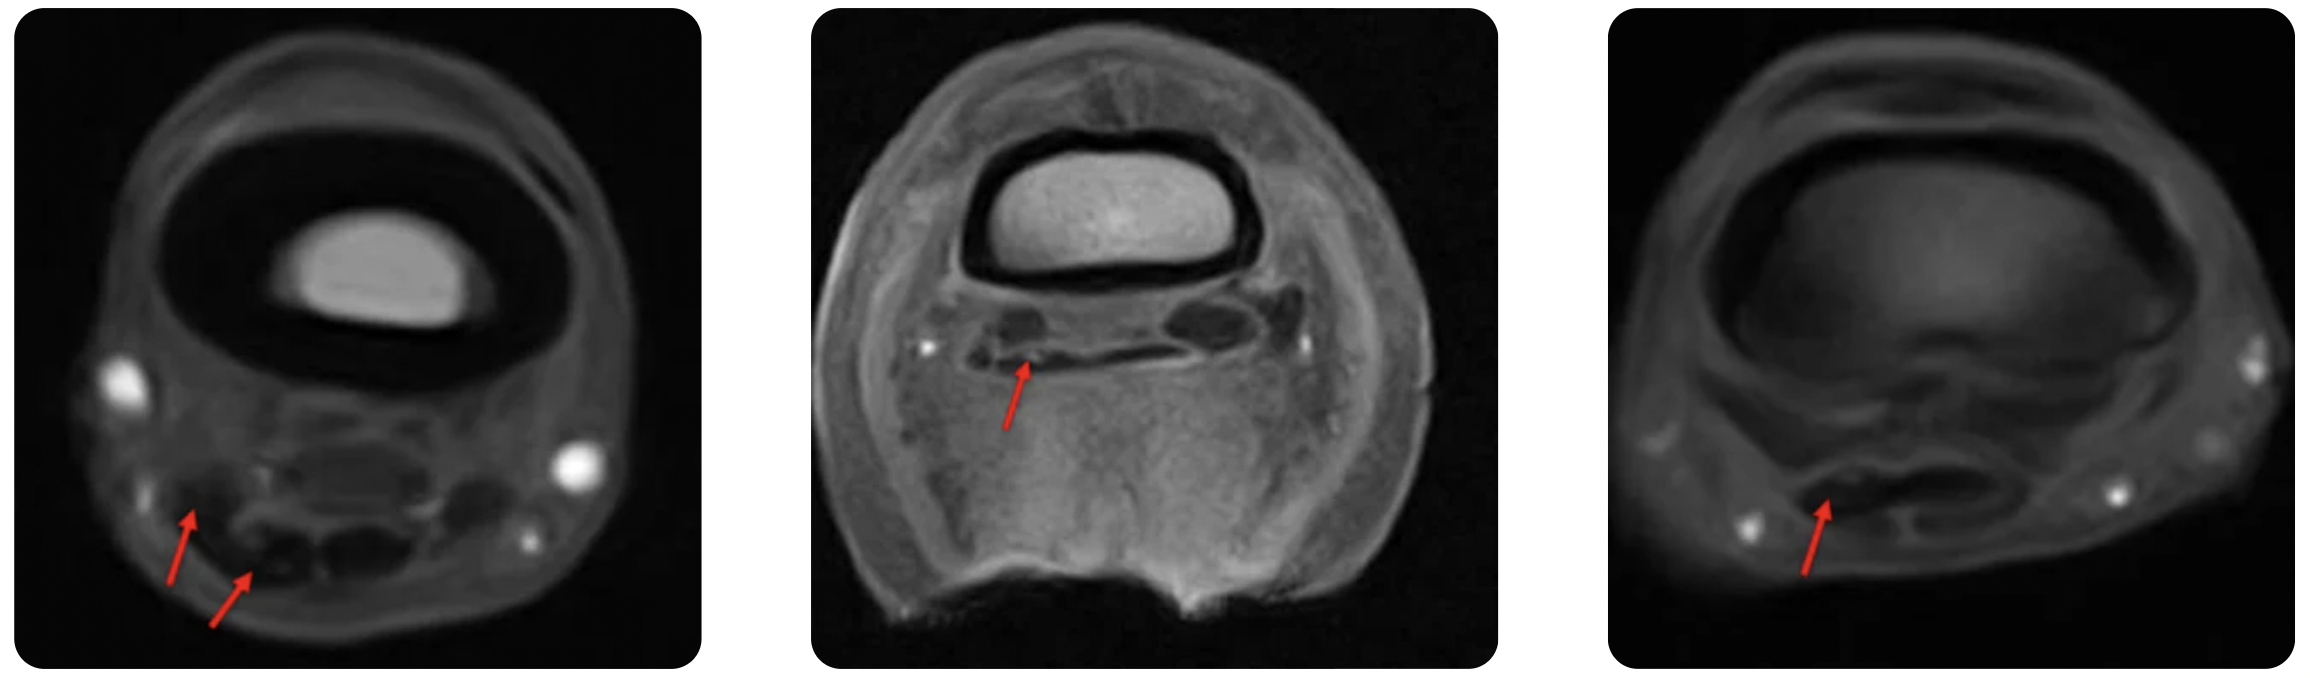

MRI confirmed an extensive lesion in the medial lobe of the DDFT, extending from distal P1 to its insertion on P3. Additional findings included moderate navicular bursitis in the left forelimb, an enlarged synovial fossa of the navicular bone with mild STIR hyperintensity—consistent with fluid-like material within the endosteal aspect of the navicular bone—mild injury to the medial branch of the superficial digital flexor tendon, mild-to-moderate synovial effusion of the distal interphalangeal joint, and sclerosis with moderate osteoarthritis of the fetlock joint.